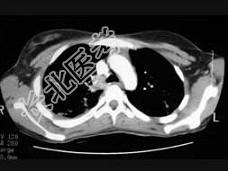

- 单项选择题女,18岁, 1年前患肺结核经抗结核治疗后好转,现发热、咳嗽、体重下降, 结合CT图像,最可能的诊断是 ( )

A、肺结核

B、肺炎

C、肺脓肿

D、肺转移瘤

E、细支气管肺泡癌